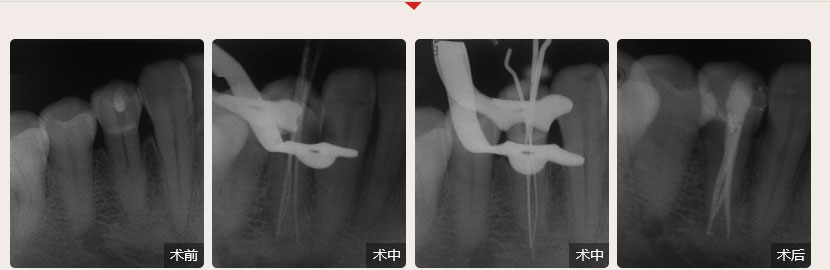

德倫口腔醫(yī)生全國根管治療技術(shù)競賽獲獎案例展示

根管治療過程